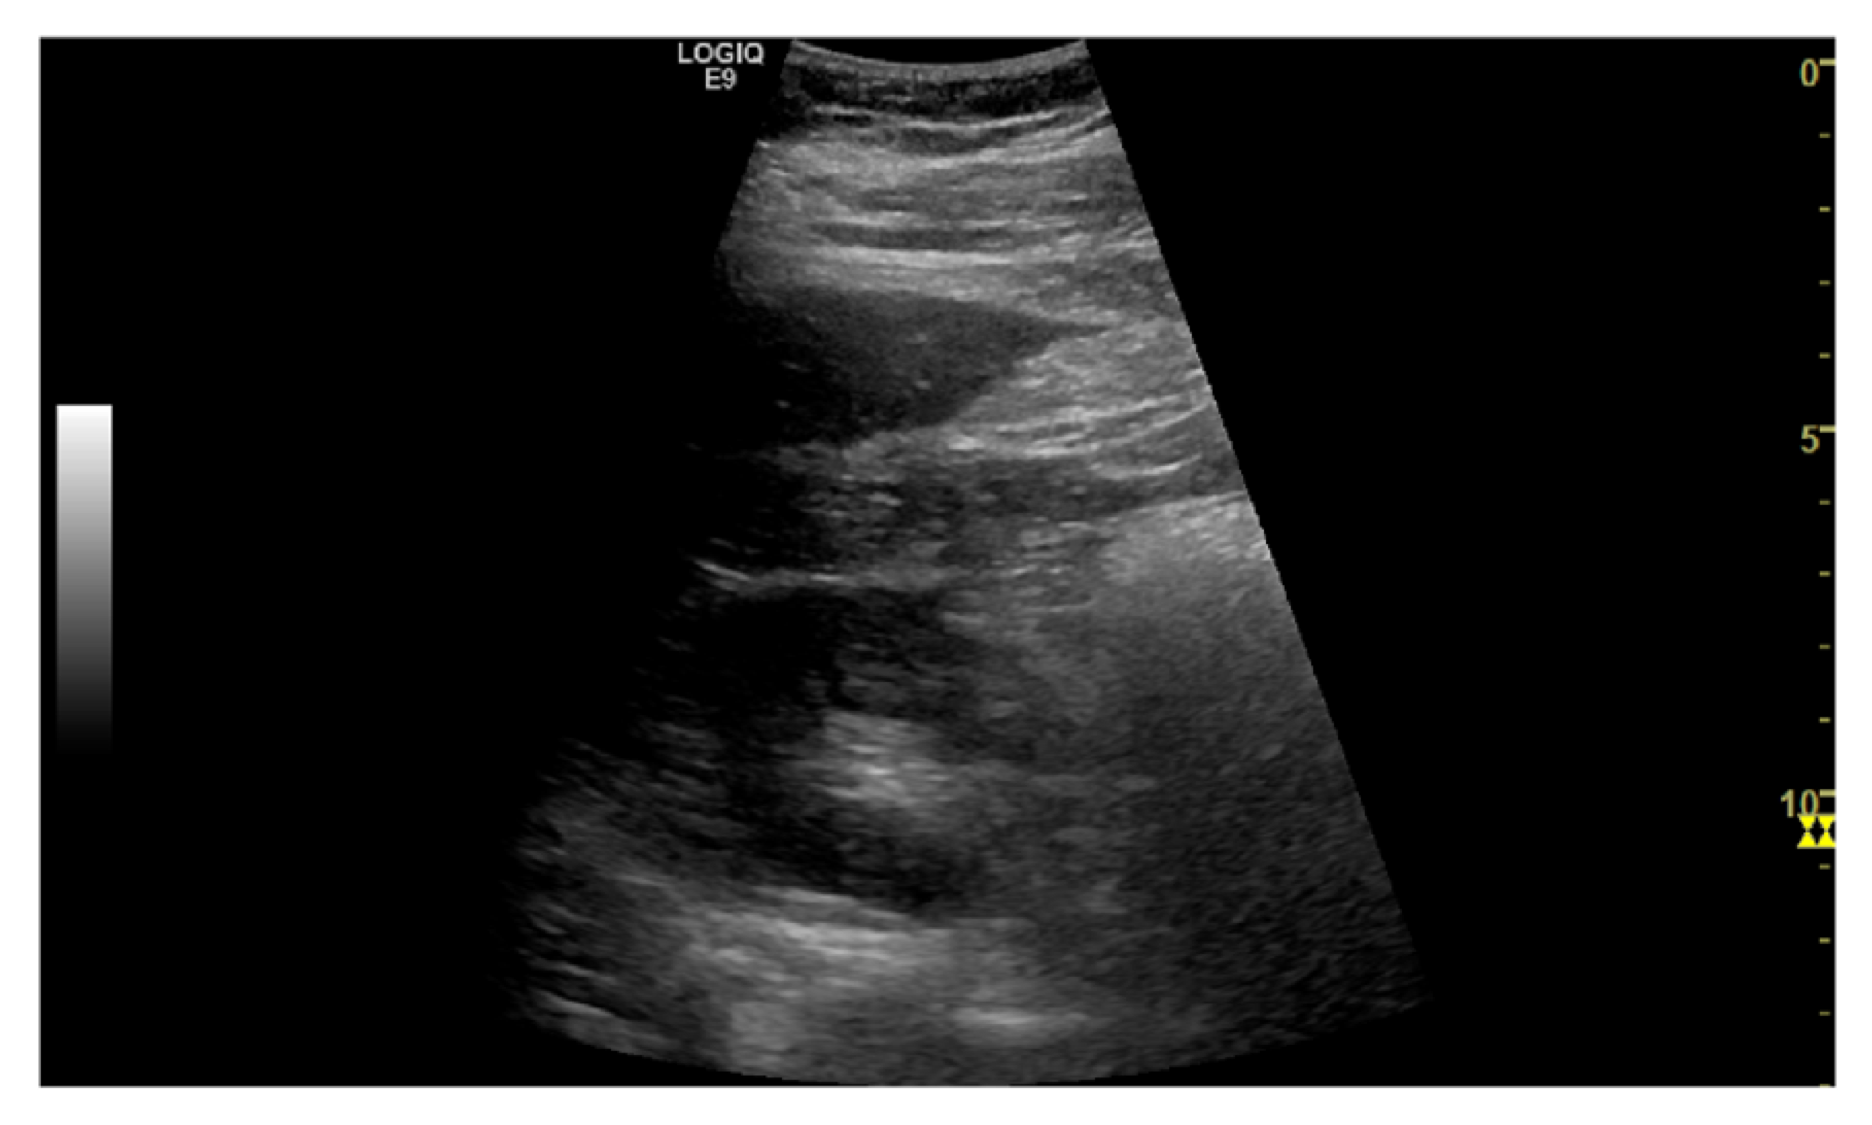

The task is to identify an optimal view for Morrison’s pouch - an anatomic site between the right lobe of the liver and the right kidney. Clinically, the view is important to identify ascites and hemoperitoneum when abnormal fluid accumulation is presented; also, it is the reference view to estimate the severity of steatosis using the hepatorenal index. Therefore, quantifying the view quality is crucial in an ultrasound examination. The images were reviewed by a board-certified radiologist and gave five different rankings as the quality measurement (Figure 4). Class 0 indicates the view does not include the liver or the kidney, and should not be used; while class 4 represent an optimal Morrison’s pouch view that will be used by an experienced operator. We used the ordinal encoding for the labels. (class 0: [0,0,0,0], class 1: [1,0,0,0], class 2: [1,1,0,0], class 3: [1,1,1,0], class 4: [1,1,1,1])

Refer to caption

(a) class 0

(b) class 1

Figure 4: Example of quality score